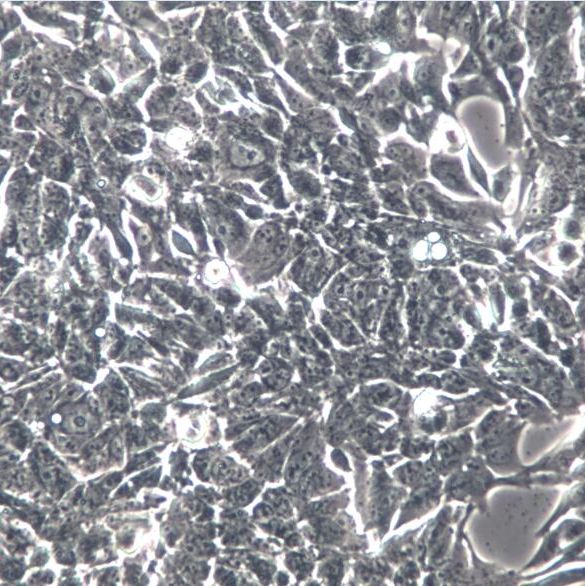

细胞名称:NCI-H358 人非小细胞肺癌细胞

组织来源:细支气管及肺泡癌

培养条件:RPMI-1640 +10% FBS

形 态:贴壁;上皮细胞样

背 景:1981年从一位开始化疗之前的患者的肿瘤组织中分离建株。超微结构研究表明细胞质中有Clara细胞的特征结构 细胞表达主要的肺表面结合蛋白SP-A的蛋白和RNA。不表达SP-B和SP-C。在软琼脂中的克隆形成效率为0.83%。